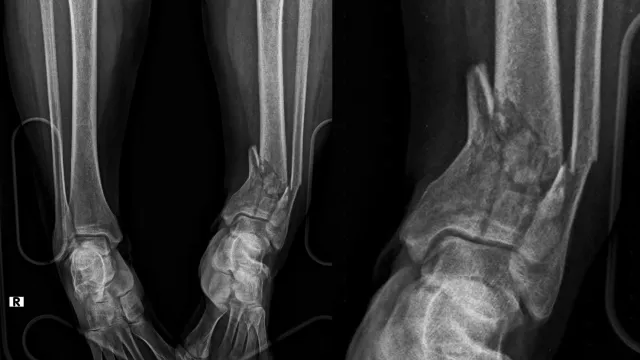

Travma Sonrası Kırık Cerrahisi: 7/24 Acil Müdahale

Devamını OkuTravma ve Kırık Cerrahisi Nedir?Travma sonrası oluşan kırıklar, çıkıklar ve yumuşak doku yaralanmaları ortopedinin en sık karşılaştığı acil durumlardı...